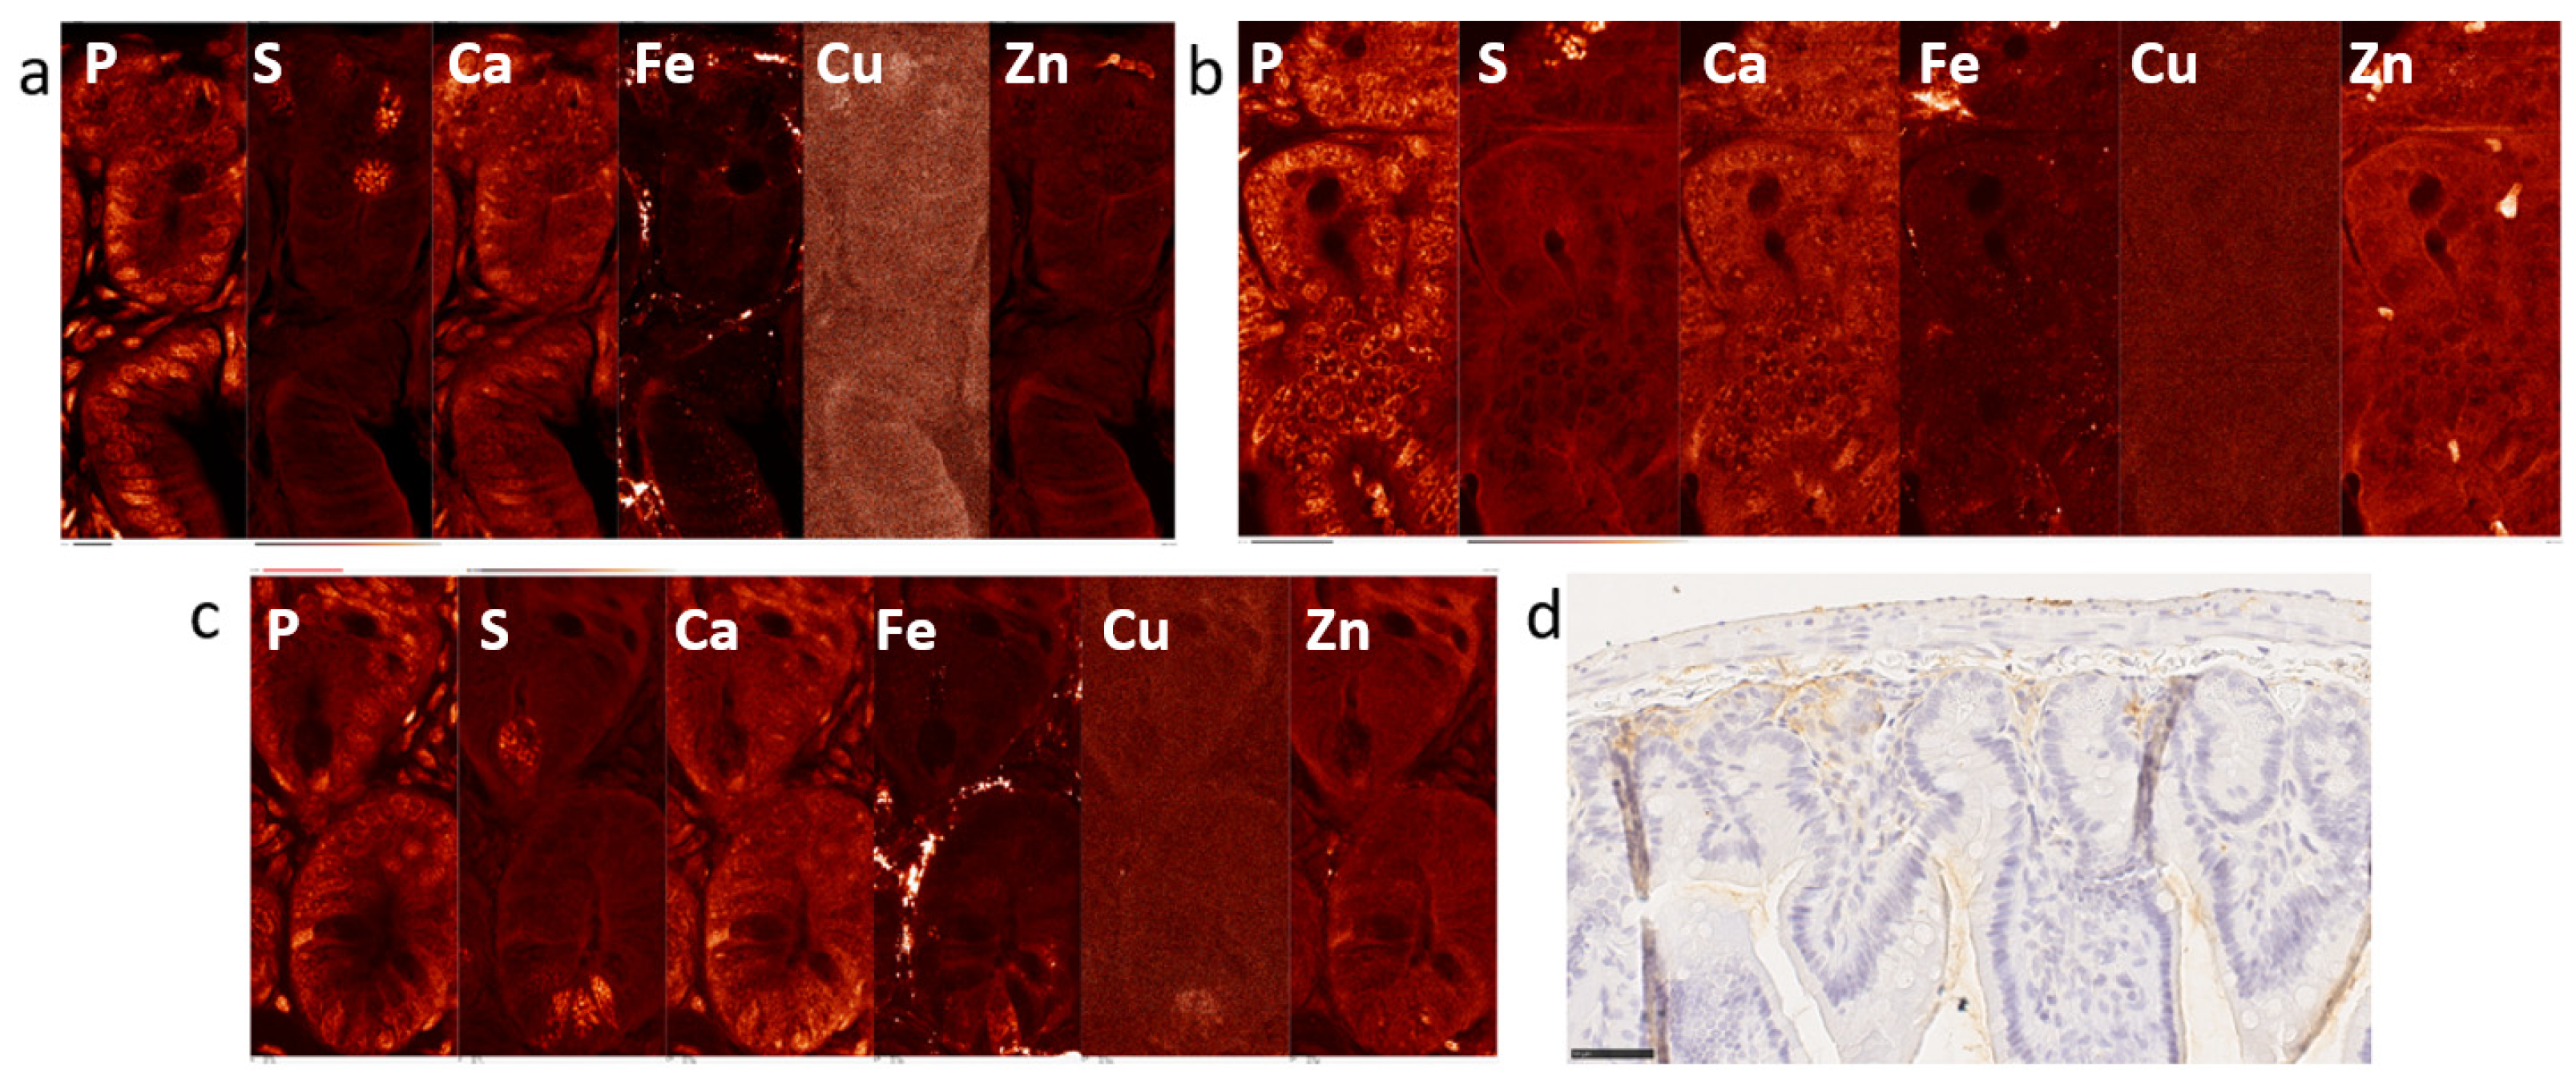

2.1. Elemental Maps of Control and Irradiated Mouse Intestine Samples